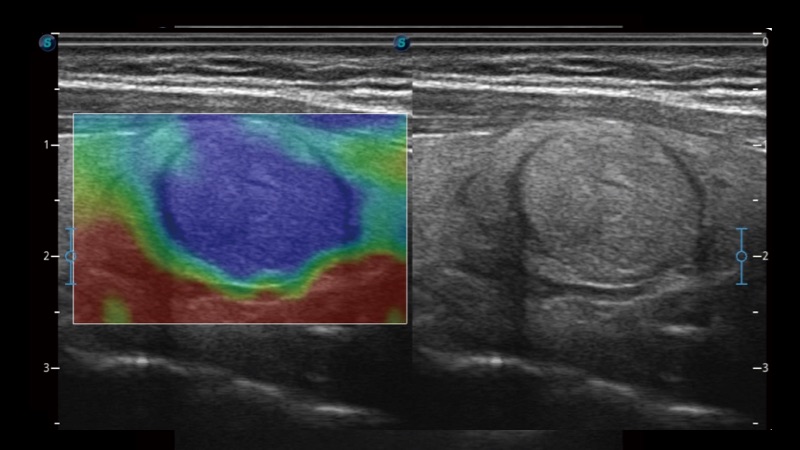

開立醫(yī)療通過不斷的技術(shù)創(chuàng)新,為大眾的生命健康提供持續(xù)關(guān)愛。P12 Plus采用全新一代超聲成像平臺(tái),新平臺(tái)旨在將真實(shí)還原組織解剖結(jié)構(gòu)作為首要目標(biāo)。平臺(tái)采用全新集成化硬件模塊,搭載新一代芯片,系統(tǒng)性能得到大幅提升,為您的診斷提供了豐富的臨床信息。優(yōu)異的圖像表現(xiàn),豐富的探頭配置,全面的應(yīng)用功能,為您日常診斷提供了可靠的助手。

彩色多普勒超聲診斷系統(tǒng)